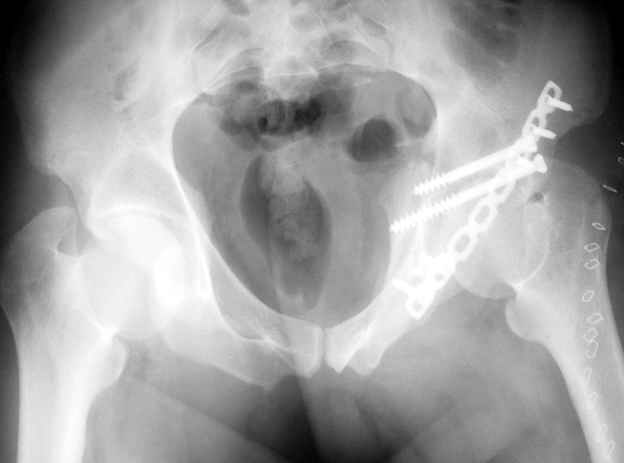

Высылаю пример еще одного случая, остеосинтез пластиной из подвздошного доступа.

Анатолий, во второй презентации, какой Ваш диагноз, не поперечный ли перелом ацетабулум? Вы написали, Ваш доступ был подвздошный, по моему мнению, ваш доступ лимитировал Вас к anterior column и постоянно надо было держать в контроле за натяжением femoral artery and vein, иначе грозит закупоркой артерии или вены, (были и такие experience), при сгибании в тазобедренном суставе, которое ухудшает и так ухудшенный доступ. По-моему, если доступ расширить, т.е. formal Ilioinguinal approach то применить пластину подлиннее 12-14 дырок на pelvic brim, через первое окно Ilioinguinal approach, т.е. Symphisis side, после рассечения места прекрепления muscle rectus abdominus, где достаточно места для 4 шурупов, тогда таким образом фиксированный перелом держится более стабильно и 4.5 мм шурупы для колонн можно было бы пропустить через пластину кзади впадины.